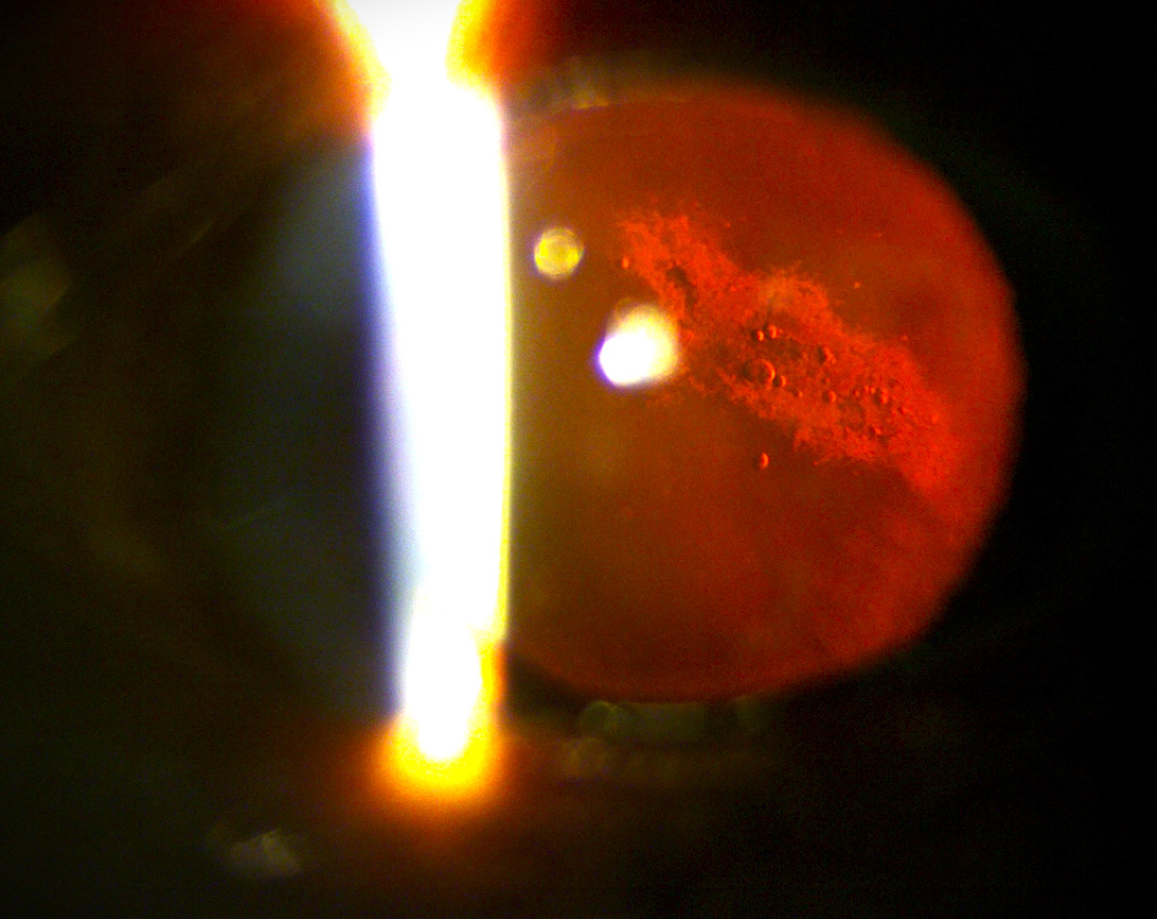

Figure 3 Slit-lamp photograph showing posterior subcapsular cataract, representing long-term radiation-associated lenticular changes observed in astronauts during or after prolonged space missions.